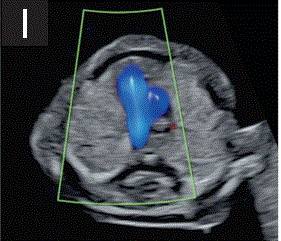

(3.6)头部下方的平面显示了两个丘脑和后颅窝区域,其中大脑脚和西尔维乌斯导水管、第四脑室和未来的大池为充液结构(图2f)。

胎儿mt是什么检查什么疼吗【文献学习/规范指南】ISUOG实践指南(2023更新): 11-14周胎儿超声检查(全文)_https://www.jmylbn.com_新闻资讯_第11张

图2 11+0至14+0周时,可作为详细胎儿超声检查的一部分获得的解剖图。

(f) 胎儿头部的横断后颅窝切面,显示丘脑、小脑、第四脑室、脑室导水管和大池。